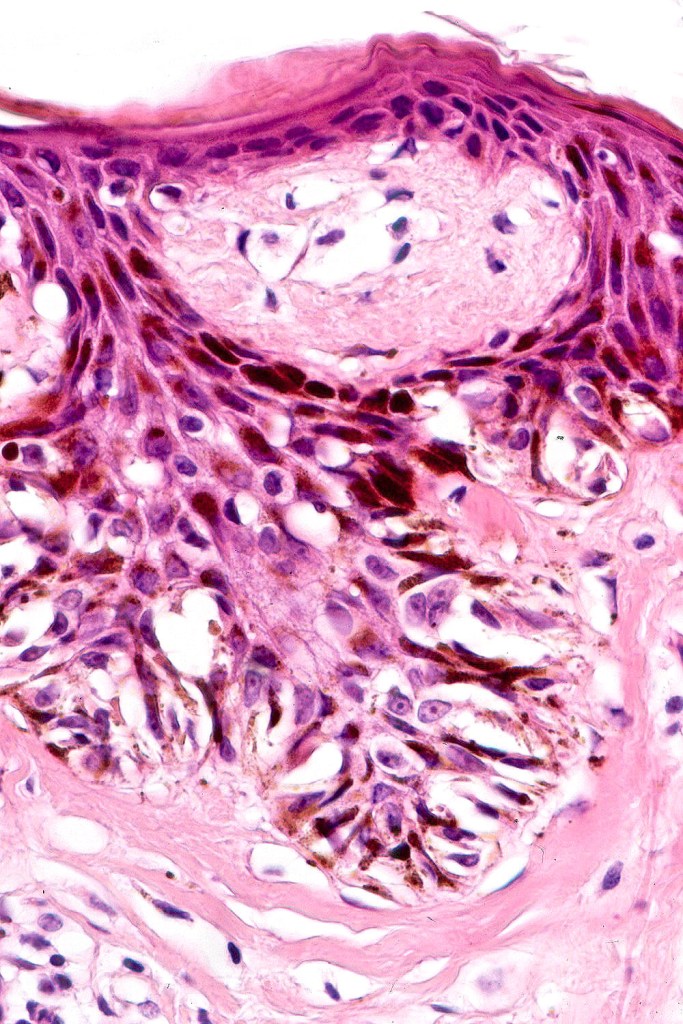

•Architectural disorder- lentiginous and nested, nests abnormally located (at the sides of the rete ridges & overlying the dermal papillae in addition to the tips of the rete ridges rather than solely occupying the tips of the rete ridges as is seen in banal nevi), horizontal orientation & bridging between junctional nests (this should not be confused with bridging between adjacent rete ridge squamous epithelium)

•Host response- eosinophilic & lamellar fibroplasia, increased vascularity, lymphocytic infiltration & pigment incontinence

•In compound lesions, the nest size should be smaller than the junctional ones and the degree of atypia the same or less

Dysplastic nevus in the majority of cases is instantly recognizable, often at low power. The most important differential diagnosis is obviously melanoma. In junctional lesions, widespread/uniform high grade atypia, frequent mitoses and Pagetoid spread are indicative of in situ melanoma. In compound lesions, dermal nests larger than junctional ones, expansile dermal nests, severe atypia and mitotic activity indicate the presence of melanoma